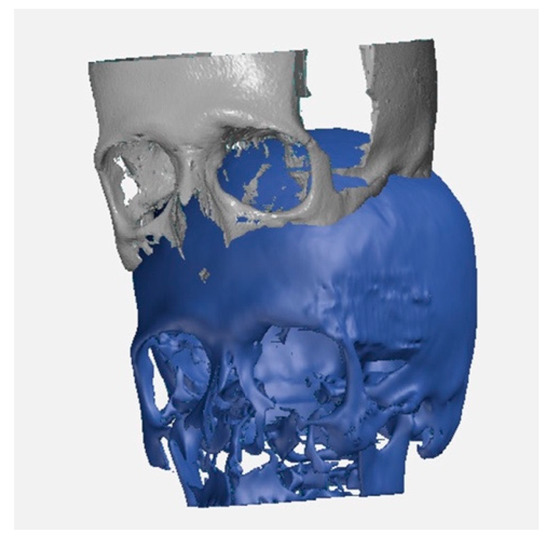

- Case #5: After 11 days post-surgery a CT was performed to check the complete removal of the tumor and that the SB was integrating without causing foreign body reaction or inflammation. After 2 years post-surgery, osteointegration was fully successful, with the reconstruction of the temporal and sphenoid bone. The bone was perfectly regenerated, and the patient’s cranial anatomy was completely reconstructed (Figure 5e). When we compared the two regions of interest in the post-surgery CT, we observed that the second one included a greater amount of bone. The bone was grown not only within the SB plaque but it was also remodeled to restore the correct skull anatomy; as a result, the right and left sides were symmetrical.